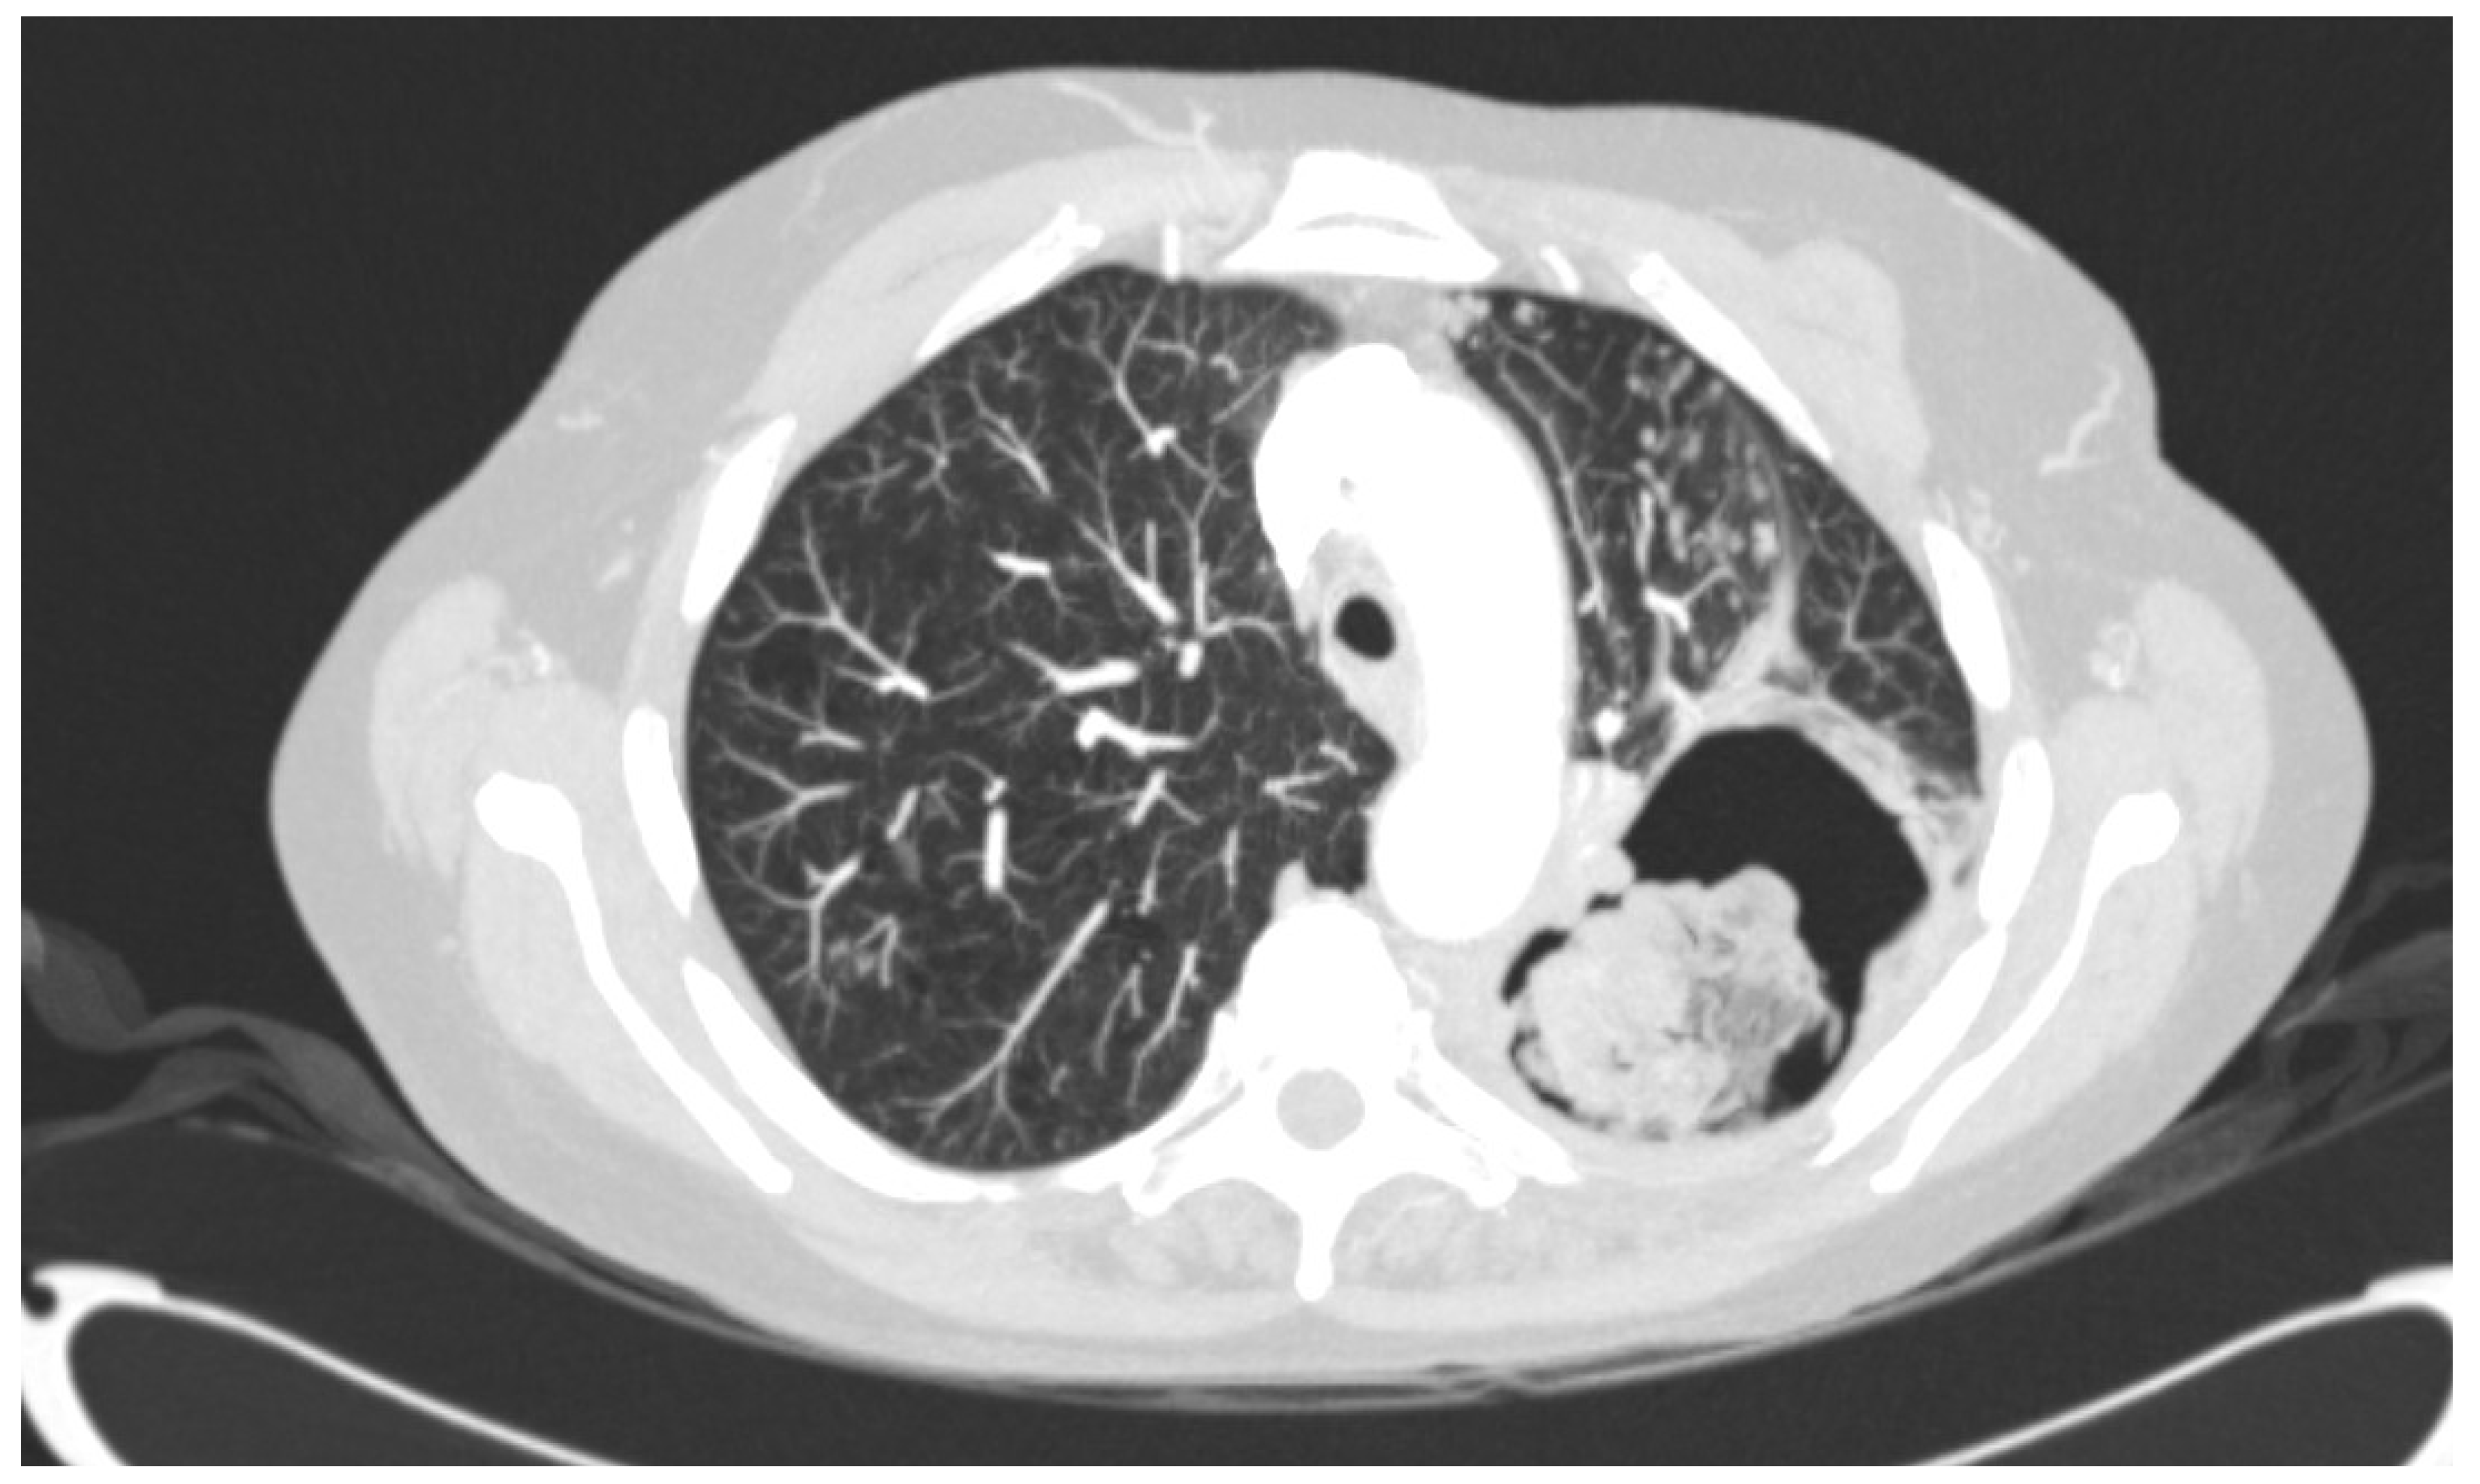

2.1. Origin of Strains and Antifungal Treatment

3.1. Strains, Phenotypical Analysis and Genotyping